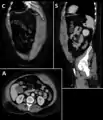

Rectus sheath hematoma

A rectus sheath hematoma is an accumulation of blood in the sheath of the rectus abdominis muscle. It causes abdominal pain with or without a mass.